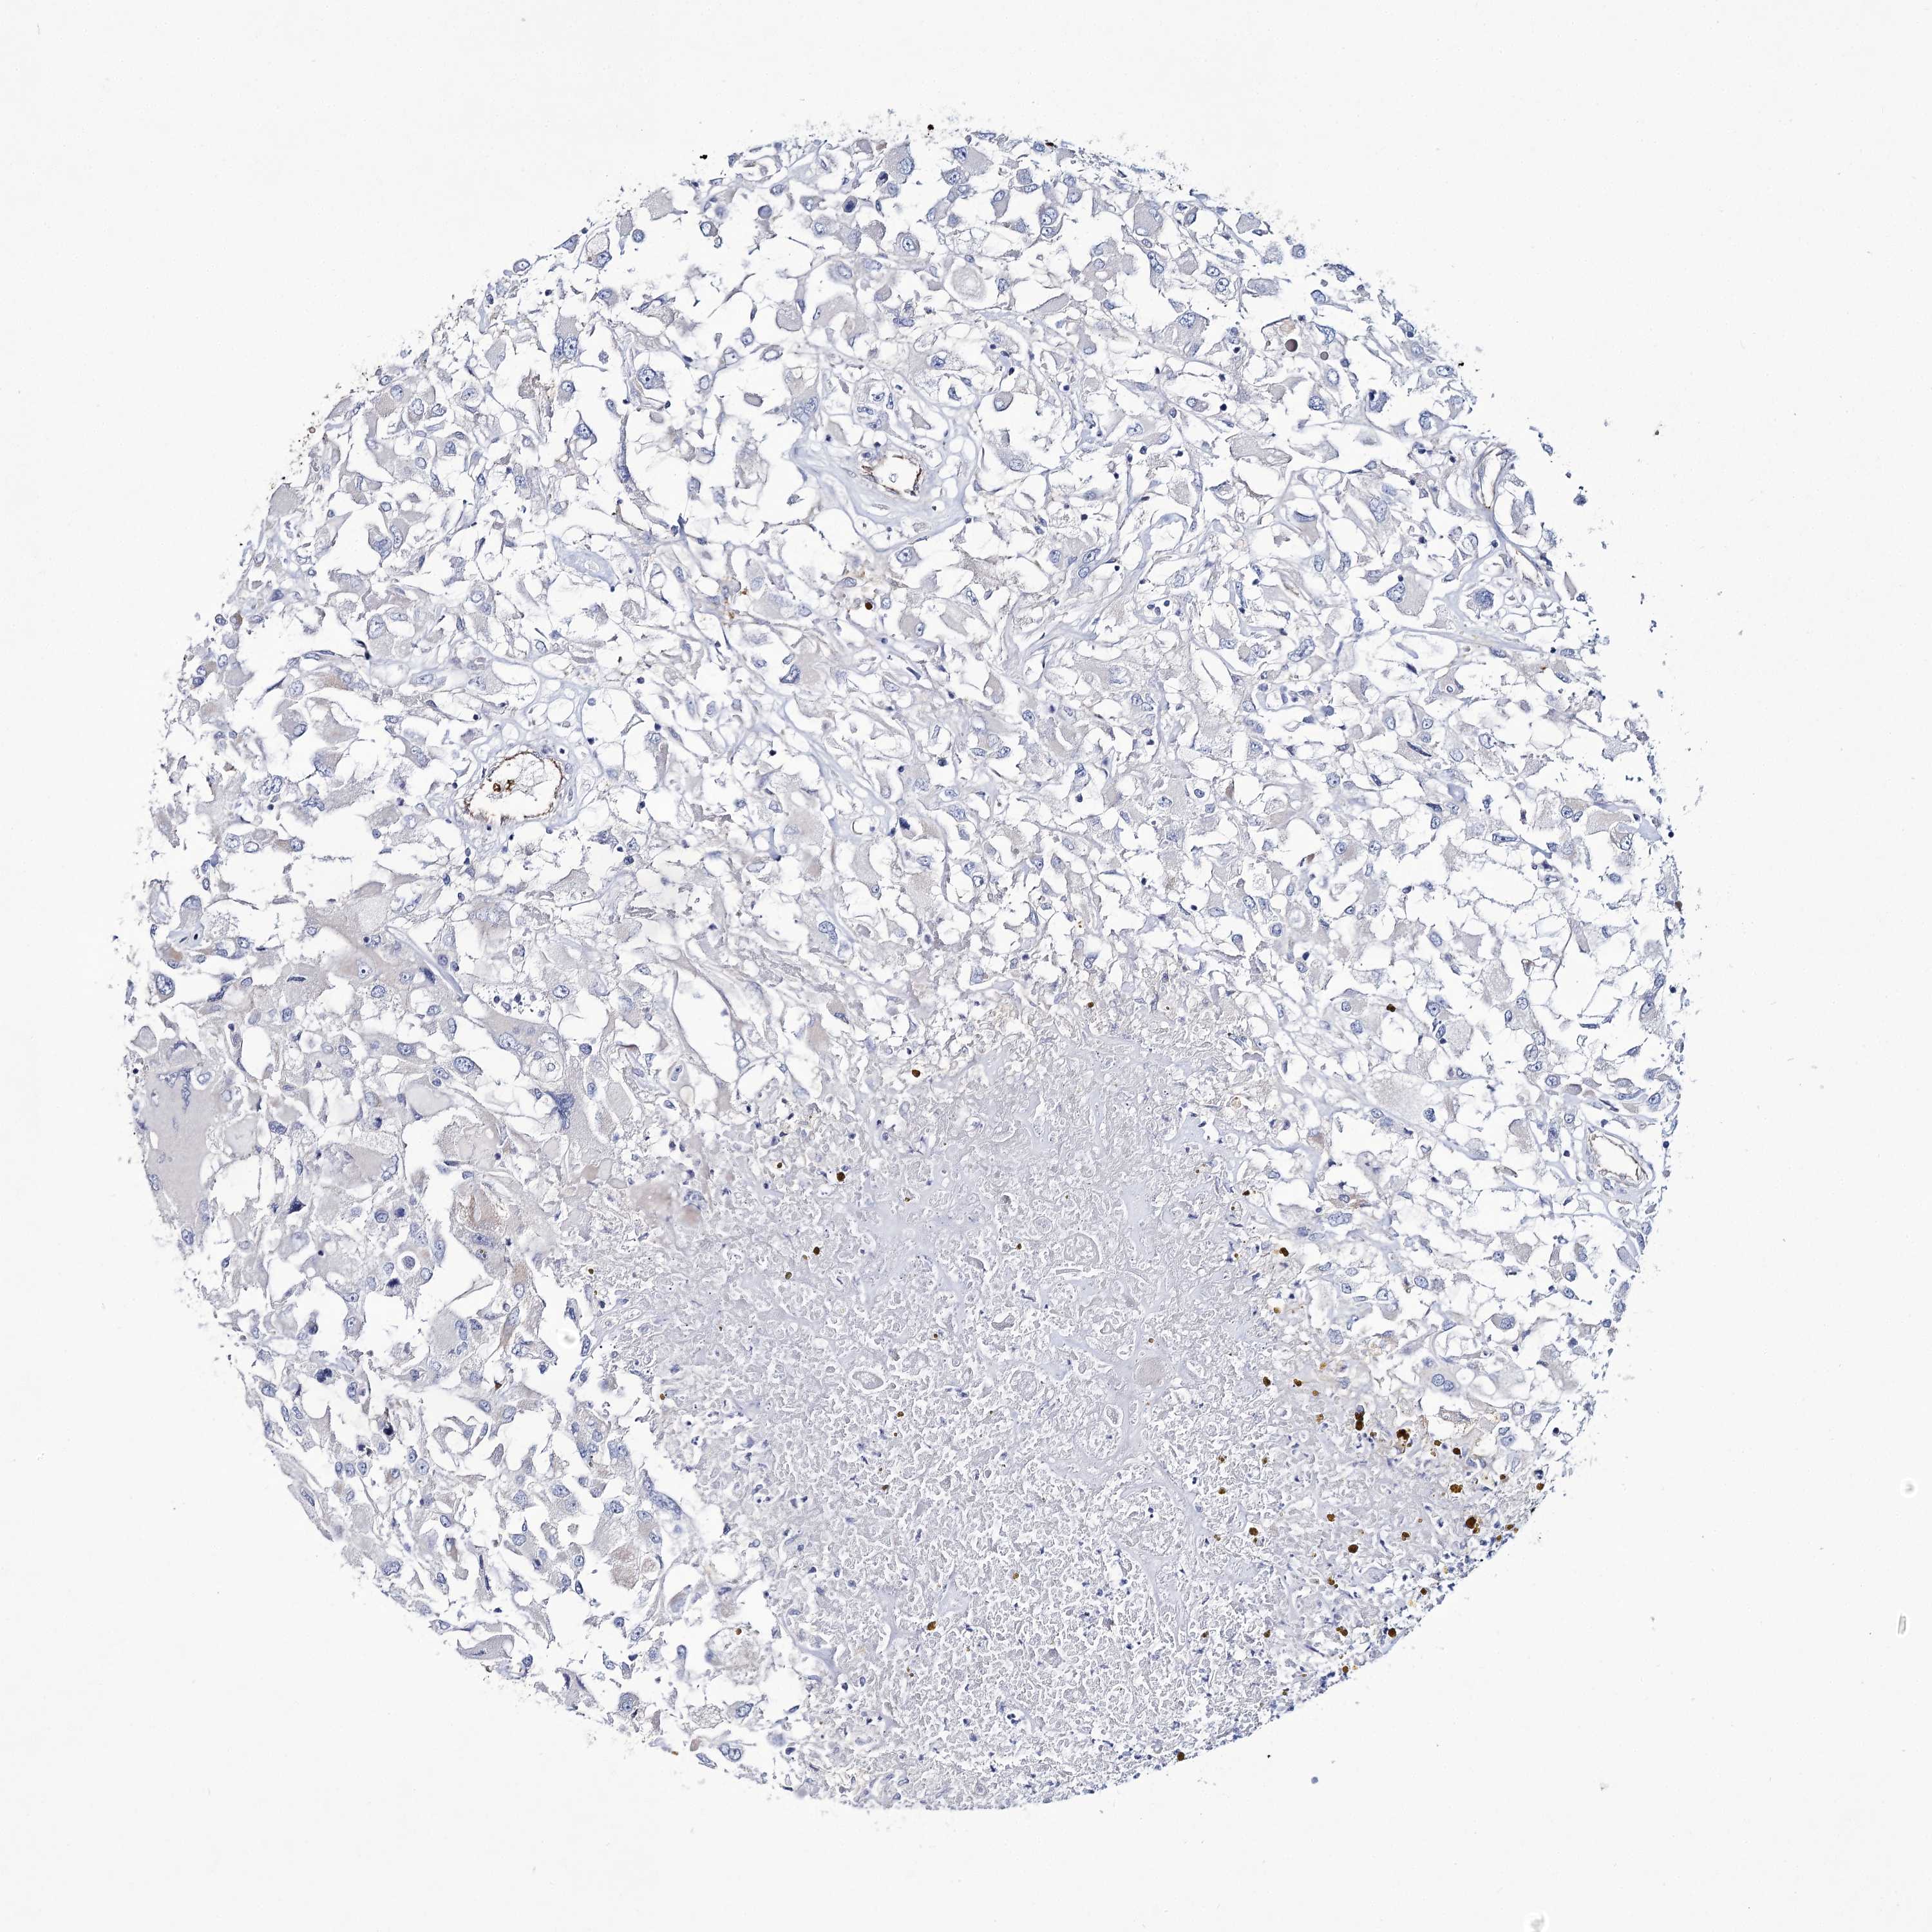

KIDNEY RENAL PAPILLARY CELL CARCINOMA (TCGA) - Interactive survival scatter ploti

The Survival Scatter plot shows the clinical status (i.e. dead or alive) for all individuals in the patient cohort, based on the same data that underlies the corresponding Kaplan-Meier plots. Patients that are alive at last time for follow-up are shown in blue and patients who have died during the study are shown in red.

The x-axis shows the expression levels (FPKM) of the investigated gene in the tumor tissue at the time of diagnosis. The y-axis shows the follow-up time after diagnosis (years). Both axes are complimented with kernel density curves demonstrating the data density over the axes. The top density plot shows the expression levels (FPKM) distribution among dead (red) and alive patients (blue). The right density plot shows the data density of the survived years of dead patients with high and low expression levels respectively, stratified using the cutoff indicated by the vertical dashed line through the Survival Scatter plot. This cutoff is automatically defined based on the FPKM cutoff that minimizes the p-score. The cutoff can be changed by dragging the vertical line or by entering a cutoff value in the square labeled "Current cut-off".

Under the Survival Scatter plot the p-score landscape (black curve; left axis) is shown together with dead median separation (red curve; right axis). Dead median separation is the difference in median mRNA expression between patients who have died with high and low expression, respectively. It is calculated as follows: median FPKM expression of dead patients with high expression - median FPKM expression of dead patients with low expression. This is intended to aid the user in visually exploring custom cutoffs and the associated p-scores and dead median separation.

Individual patient data is displayed and can be filtered by clicking on one or more of the category buttons on the top of the page. Categories describing expression level and patient information include: high, low, alive, dead, female, male and tumor stages. The scale of the x-axis can be toggled between linear and log-scale by clicking on the "x log" button. Mouse-over function shows TCGA ID, patient information and mRNA expression (FPKM) for each patient.

& Survival analysisi

Kaplan-Meier plots summarize results from analysis of correlation between mRNA expression level and patient survival. Patients were divided based on level of expression into one of the two groups "low" (under cut off) or "high" (over cut off). X-axis shows time for survival (years) and y-axis shows the probability of survival, where 1.0 corresponds to 100 percent.

GBF1 is not prognostic in Kidney Renal Papillary Cell Carcinoma (TCGA)

Best expression cut offi